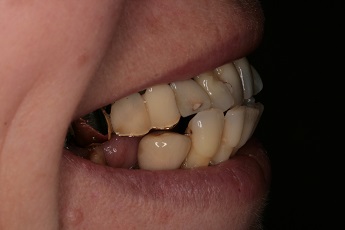

3) fotodokumentace - fotografie stavu chrupu a otisky na studijní modely

Fotodokumentace a model se provádí u pacientů s potřebou kompletní rekonstrukce chrupu.

Foto 9-13: Fotodokumentace situace v ústech - vlevo, vpravo, uprostřed, v horní a dolní čelisti.

Foto 14, 15: Vlevo zuby v úsměvu před ošetřením chrupu. Vpravo fotografie skusu zubů.